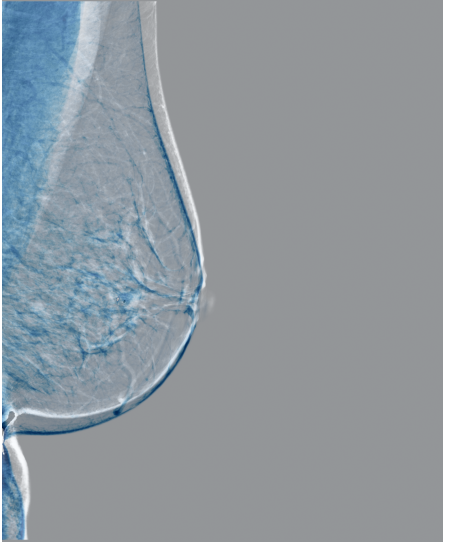

Refer to caption

(a) FeatAlign

(b) FeatAlignReg

(c) ImgFeatAlign/ImgAlign

(d) FeatAlign

(e) FeatAlignReg